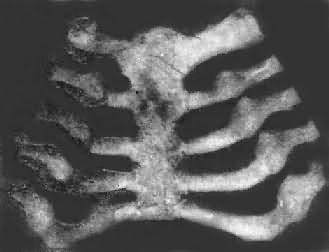

肋骨和肋软骨结合处的改变与长骨骺板及干骺端的改变相似,由于软骨及骨样组织的堆积,致使肋骨和肋软骨的结合部呈结节状隆起。因多个肋骨同时受累,故结节状隆起排列成行,形似串珠,称为佝偻病串珠(rachitic rosary)(图17-11),常是佝偻病的较早期表现之一。此外,肋骨因含钙量少,缺乏韧性,同时由于膈在呼吸时的长期牵拉,在胸壁前部左右两侧各形成横行的沟形凹陷,称为Harrison沟。又因在呼吸时,肋骨受肋间肌的牵拉而下陷,使胸骨相对向前突出,形成鸡胸畸形。

图17-11 佝偻病的肋骨

肋骨和肋软骨结合部呈结节状隆起,排列成行,形似串珠